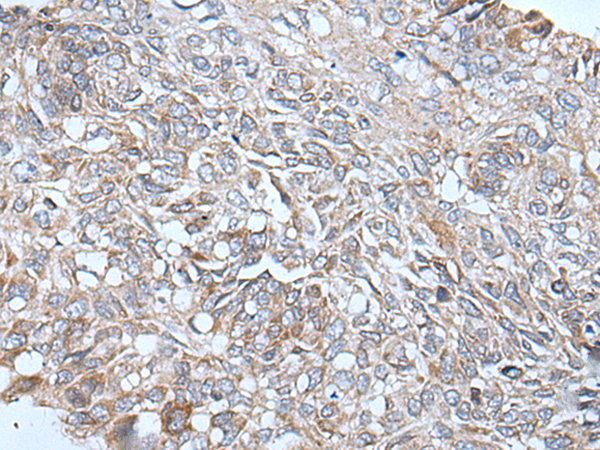

分类: 科研抗体货号: P12837别名: ZAP; ZC3H2; ARTD13; PARP13; FLB6421; ZC3HDC2应用: IHC反应种属: Human